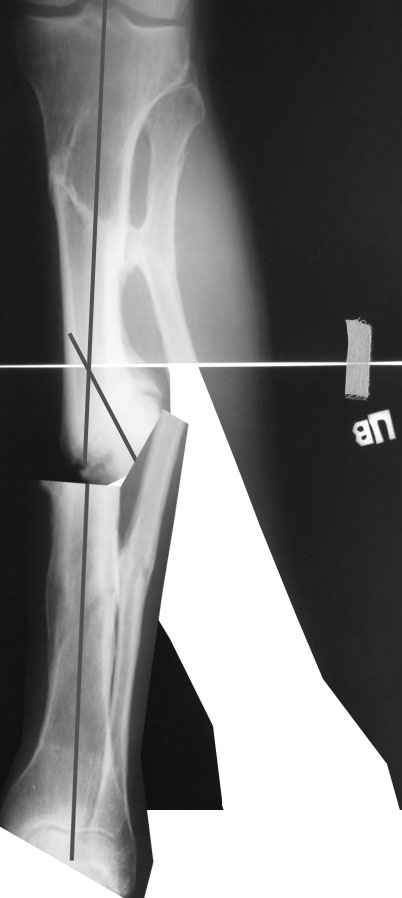

Одномоментно такой угол устранить трудно, сильно натянутся ткани по наружной поверхности голени. Может и стопа повиснуть. А что по второй проекции?

Мы бы сделали после остеотомии малоберцовой и аппаратной коррекции. Большеберцовую можно исправить за счет растяжения пседартроза. Можно и сделать поперечную остеотомию чуть дистальнее несращения, в этом случае будет удобный вход в периферический отломок. А зону несращения пройти разверткой просто по прямой. Схема в приложении.